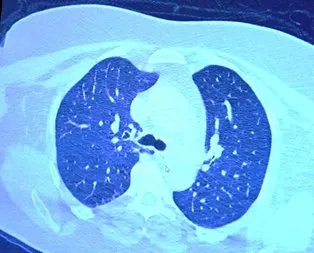

TOMOGRAFİ HABERLERİ

TOMOGRAFİ ile ilgili en güncel gelişmelere, haber başlıklarına ve detaylı bilgilere bu sayfadan ulaşabilirsiniz. İlginizi çeken içeriklere hızlıca göz atabilir ve aradığınız bilgileri kolayca bulabilirsiniz. TOMOGRAFİ sayfası, sizin için özenle hazırlanmış tüm ilgili haberleri, yazıları ve kaynakları bir arada sunar. Gündemden, analizlerden veya ilgi çekici içeriklerden haberdar olmak için sayfamızı takipte kalın!